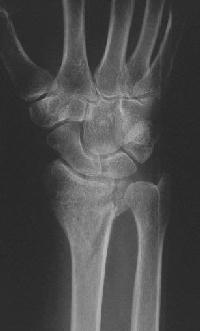

Clinical Example: Distraction plate fixation distal radius fracture

distal radius fracture

distraction plate